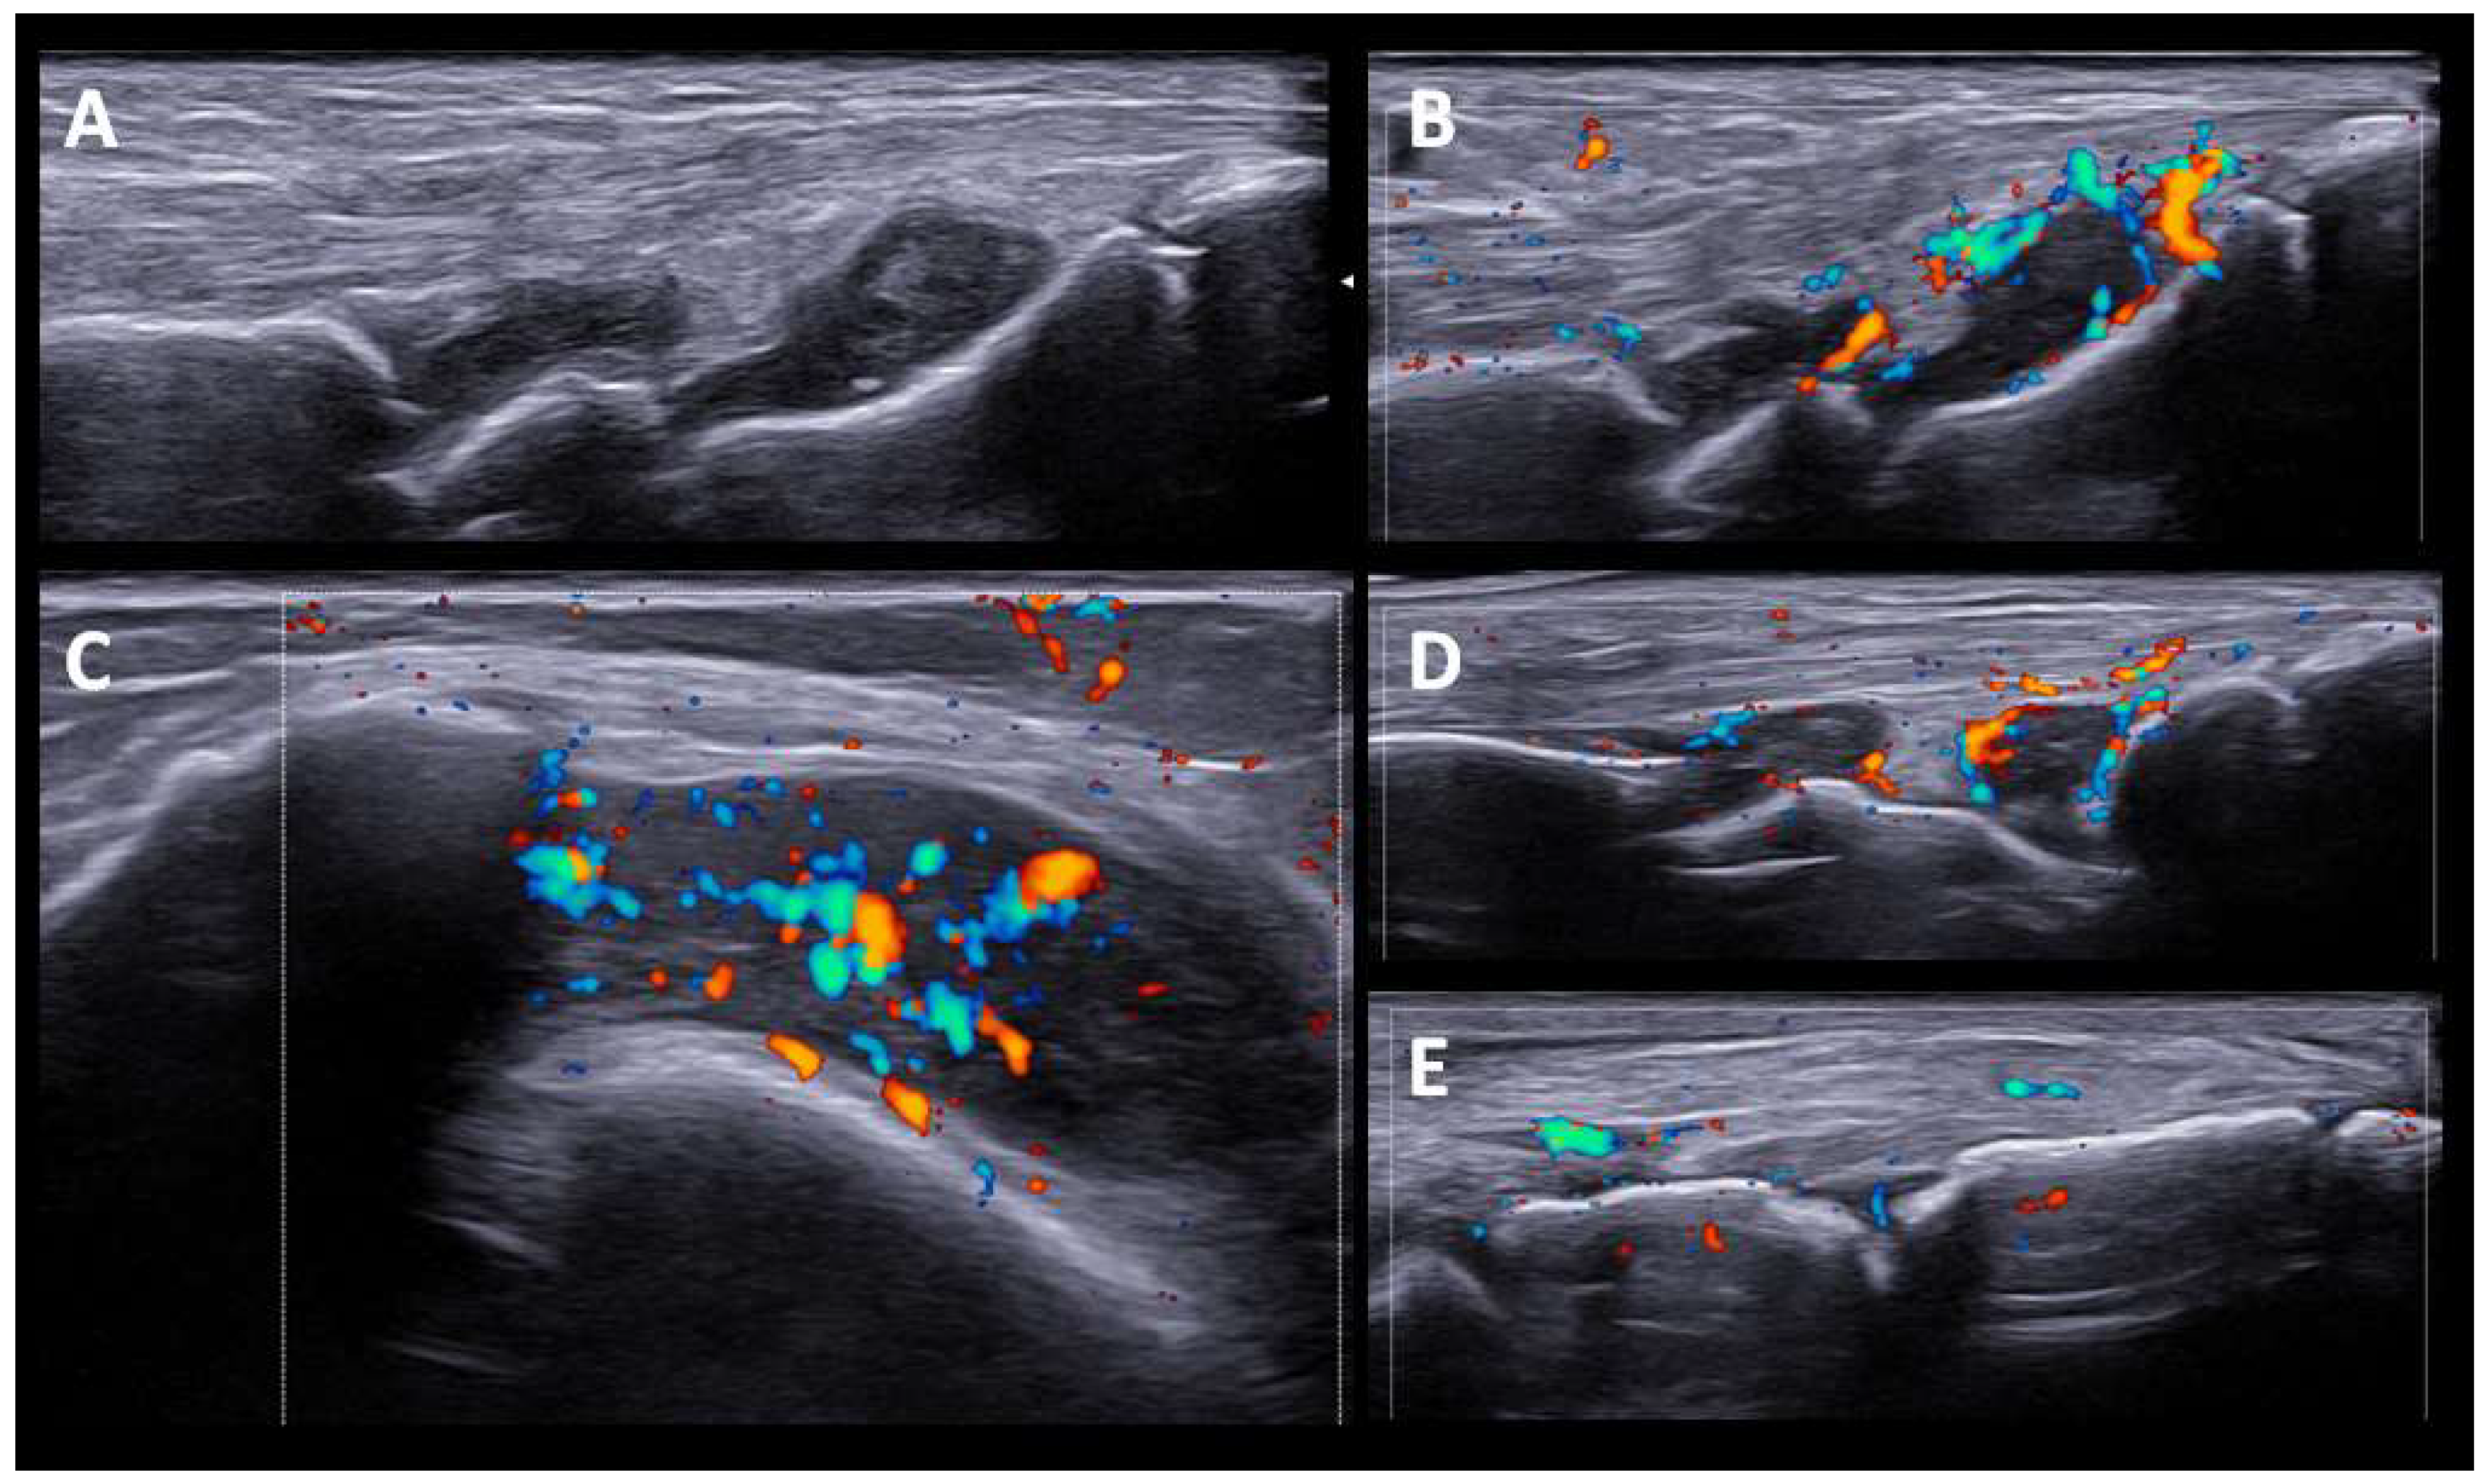

Five patients had a PMR-like syndrome. In three, the imaging test was made before the start of glucocorticoid treatment. US showed synovitis of the hip and trochanteric bursitis, and bilateral inflammatory bicep tenosynovitis, in one patient. In the other two patients, the shoulders and hip joints were studied by PET/CT scan, showing a periarticular pattern in the shoulder and pelvic girdle (see further comments below). We also identified sonographic changes in the wrists and hands in patients with PMR-like disease, affecting not only the wrists but also the MCPs, and finger tenosynovitis (Figure 2).

One patient had dactylitis in two fingers. US revealed soft tissue thickening with PD signal, subcutaneous edema, and inflammatory tenosynovitis in the flexors of the hand (Figure 3). The two patients with monoarthritis (carpus and knee) had a history of rheumatic disease (chondrocalcinosis and HLA-B27 associated uveitis). In these patients, SH and grade 2 PD signals were detected. The distribution of joint involvement (synovitis and tenosynovitis) according to the arthritis patterns after US evaluation is shown in (Figure 4).

It has been reported that ICI-induced PMR has US and FDG-PET/CT results comparable to those seen in regular PMR [26]. We also found characteristic US findings in PMR-like ICI-induced patients similar to those previously described (i.e., glenohumeral and hip joint synovitis, bicipital tenosynovitis, and subacromial bursitis) [26]. Peripheral symmetrical synovitis and tenosynovitis, clinically subtle or not evident at all, in addition to rhizomelic involvement was a notable finding. Although peripheral synovitis and tenosynovitis are frequently reported in PMR, it is usually oligoarticular and transient [31]. As in other studies of typical PMR [32], we found that in patients with ICI-induced PMR, tenosynovitis of the flexor tendons of the hand was the most frequent US finding of peripheral involvement. Interestingly, in treated patients, we found not synovitis, tenosynovitis, or bursitis in the shoulders and pelvic girdles, which seemed to have resolved with glucocorticoid treatment. However, peripheral synovitis/tenosynovitis in the hand joints remained evident.

In particular, in one patient with dactylitis (Figure 3), US findings included soft tissue thickening, subcutaneous edema, flexor tenosynovitis, and synovitis, without major differences with previously-described typical PsA [33]. US findings of oligoarthritis and monoarthritis patterns showed high levels of SH and PD signals, with no particularities with respect to inflammatory arthritis.

Figure 2. US findings in PMR-like pattern. (A). Hip joint (longitudinal view) with moderate effusion. (B). Bicipital tenosynovitis with power doppler signal grade 2. (C). Synovitis at second MCP joint with Power Doppler grade 2. (D). Tenosynovitis of hand flexor tendon with Power Doppler grade 2.

Figure 3. US findings in PsA-like pattern. Hand dactylitis. The US findings in PsA-like pattern. Hand dactylitis. The US findings include soft tissue thickening, subcutaneous edema and flexor tenosynovitis (A,B) with Power Doppler signal (C,D).